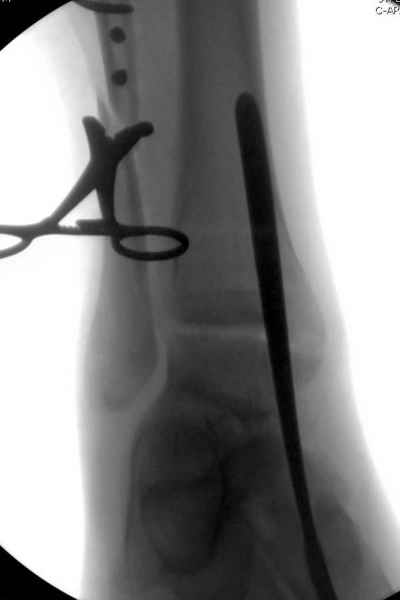

Мы бы, сблизив берцовые кости чрескожно наложенным репозиционным зажимом, провели позиционный межберцовый винт чуть ниже пластинки в положениий максимального тального сгибания стопы и ... на следующий день разрешили бы полностью наступать без гипса, брейса и т.п., но в обуви с небольшим каблуком 2-3 см и супинатором. Через месяц-полтора -винт удалить (если конечно не сломается).

Перелом типа Вебер С с эверсионным механизмом травмы всегда сопровождается повреждением дистального межберцового синдезмоза, поэтому вместе с фиксацией переломов лодыжек( малоберцовой кости) автоматом выполняется фиксация синдесмоза винтом, который обычно удаляется через 8 недель -

перед началом полной нагрузки на ногу.

Спустя 4 недели закрытая ( без отрытия зоны синдесмоза) репозиция может оказаться проблематичной, но все равно стоит попробовать из 1см разреза ввести тягловый винт и нтраоперационно проконтролировать межберц. синдесмоз. Предварительно стоит обсудить с больным вероятность открытия синдесмоза при безуспешности закрытой репозиции.

С мнением «провести позиционный межберцовый винт чуть ниже пластинки в положениий тыльного сгибания стопы» согласен, но я бы нагрузку начал через три недели и удаление шурупа можно провести через 6-8 недель.

Для облегчения удаления сломанных шурупов (случается часто) рекомендую фиксацию двумя 3.5мм кортикальными шурупами на 3 мм длиннее, тот же сломанный шуруп легко удаляется с медиальной стороны.

Здесь похожий случай трехнедельной давности, перелом почти сросся и была укорочена малоберцовая, на операции длину малоберцовой смогли восстановить только после того, когда проксимальнее пластины ввели шуруп и использовали его как толкатель, с помощбю дистракционого инструмента (lamina spreader).